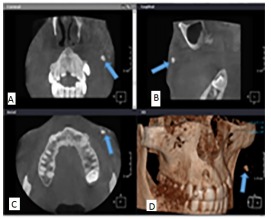

Prevalence of osteoma cutis in the maxillofacial region and classification of its radiographic pattern in cone beam CT